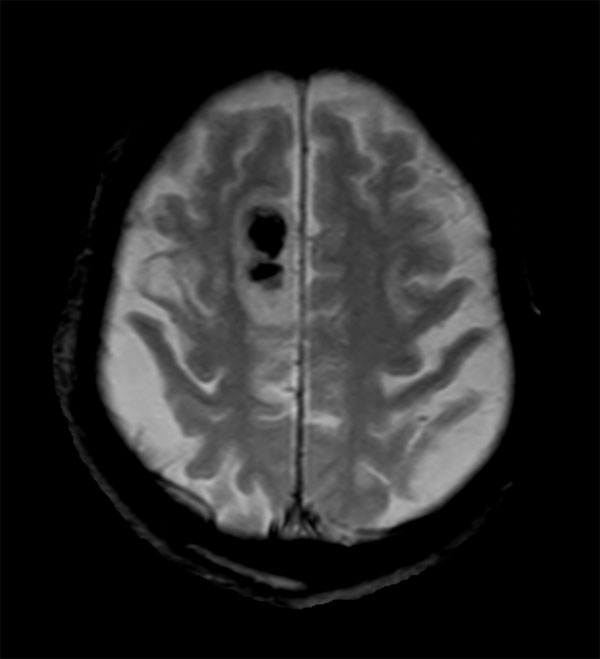

Acute stroke. Patient was brought to the first aid and directly transferred to the MRI unit. Axial studies were performed to get an overview of the stroke. Total study time is 9 minutes.

Axial T2w TSE

Axial T2* FFE